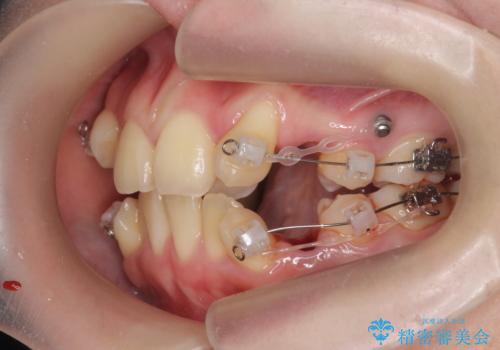

歯並びのせいで歯ブラシがしづらい マルチブラケットを用いた抜歯矯正

- 歯並びのがたつきにより歯ブラシがしづらく、今後虫歯になってしまう不安から、矯正治療を希望されて来院されました。

歯を並べるにはスペースが不足しているため、小臼歯の抜歯を4本行うマルチブラケット矯正による治療を計画します。

治療後は非常に歯ブラシがしやすくなったと、治療結果に満足いただくことができました。